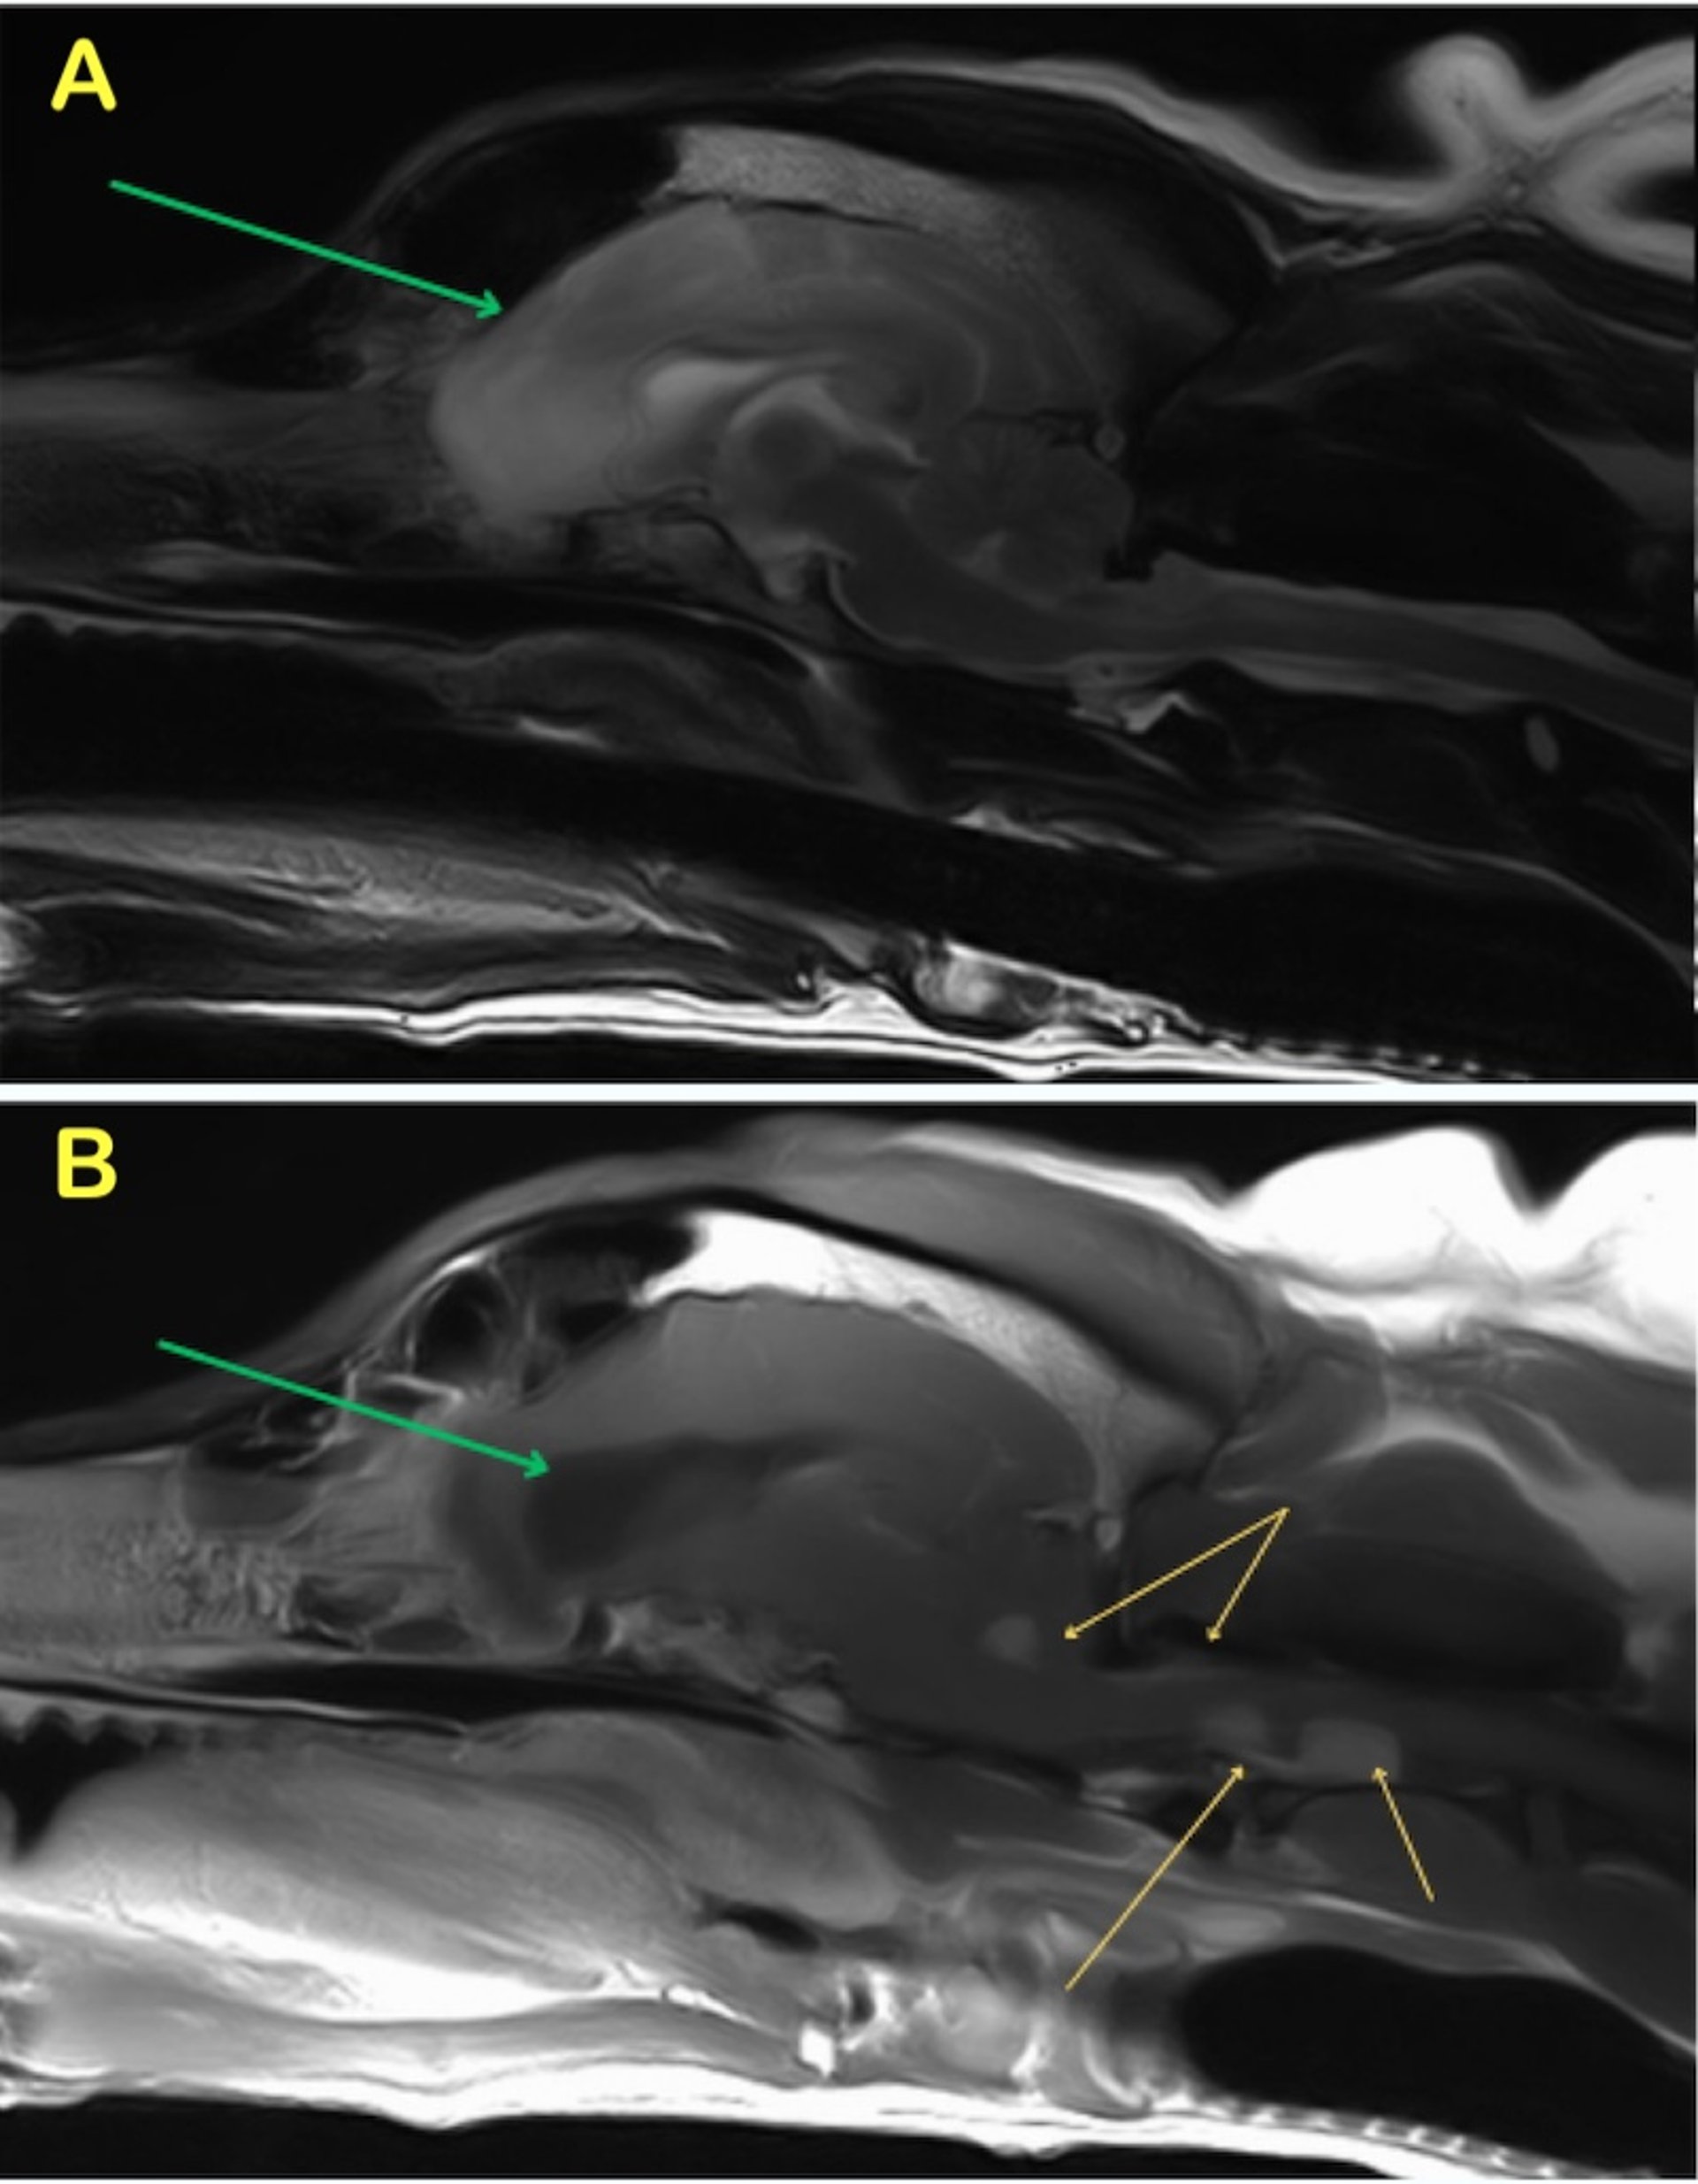

Choroid plexus tumor, MRI, dog

Presumptive choroid plexus tumor with drop metastases and obstructive hydrocephalus. T2W sagittal (A) and T1W postcontrast sagittal (B) images of the brain and cranial cervical spine of an 8-year-old pit bull–type dog that developed seizures. Green arrows denote the enlarged lateral ventricles and intracranial edema indicating obstructive hydrocephalus. Yellow arrows on the postcontrast sagittal image indicate the strongly contrast-enhancing tumor within the fourth ventricle as well as multiple metastases and meningeal involvement within the cranial cervical spine.

Courtesy of Dr. Baye Williamson.